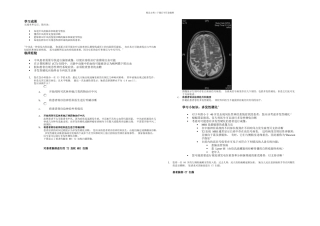

精品文档---下载后可任意编辑学习成果完成本单元后,您应该:知道中风的临床和放射学特征懂得中风的常见鉴别诊断能够辨识中风的鉴别...